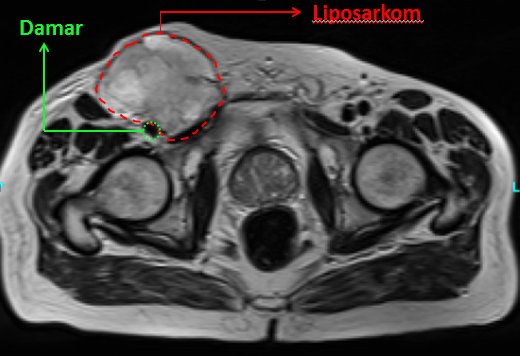

Ortopedik onkolojinin alanına giren tümörler sadece kemiklerden kaynaklanmaz. Aynı zamanda kas, damar, yağ dokusu, sinir ve eklem gibi yumuşak doku elemanlarından da köken alabilir. Örneğin kol ve bacakta yada vücudun diğer bölgelerinde gözle görülebilen yada dokunmakla hissedilebilen kitleler şeklinde olabileceği gibi bazen dışarıdan hissedilemeyecek şekilde derin yerleşimli ve yumuşak doku kökenli lezyonlar şeklinde de olabilir. Bu gibi lezyon varlığında kemik tümörlerinde olduğu gibi biyopsi yapılması temeldir. Bu şekilde doğru tanı konabilir. Tanıyı doğru koymadan tedaviye asla geçilmemelidir.

Yumuşak doku tümörleri de kemik tümörlerinde olduğu gibi iyi huylu yada kötü huylu olabilir. Kötü huylu olanları gene kemik tümörlerinde olduğu gibi “sarkom” olarak adlandırılır. Ancak bu, yumuşak doku sarkomudur. Yumuşak doku sarkomlarının tedavisi çoğu zaman cerrahidir ve geniş rezeksiyon gerektirir. Ameliyatta geniş rezeksiyon yapılarak tümör, etrafında sağlam doku ile birlikte geniş olarak çıkartılır (resim-18).

Halk arasında ‘yağ bezesi’ olarak adlandırılan ise “lipom”lardır. Lipomlar yağ dokusundan köken alır. Genellikle cilt altı yağ dokusu ve adeleler arasından kaynaklanır (resim-20). Birkaç yıldır mevcut olan yumuşak, hareketli, düzgün sınırlı kitleler şeklindedir. Ancak bazen malign değişim göstererek sarkoma dönüşebilir. Bunun adı ise “liposarkom”dur (resim-21). Lipomlar bazen vücutta çok sayıda olur. Bunun adı “lipomatozis”dir. Lipom tedavisi cerrahidir. Eğer çok büyük, kişiyi rahatsız eden, damar yada sinir basısı sonucu fonksiyonları bozan lezyonlar şeklindeyse operasyonla çıkarılır. Eğer bunlar yoksa sadece izlem yeterli olabilmektedir.